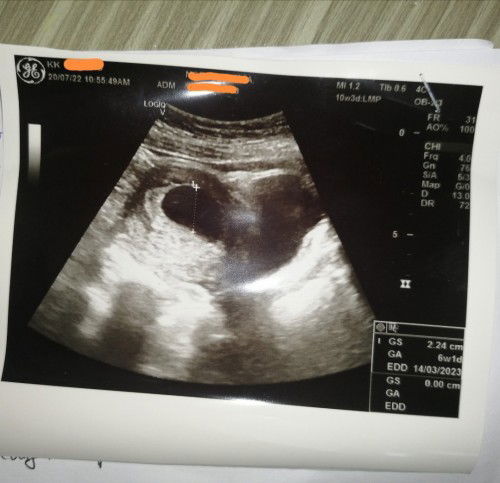

SCAN 1BULAN TP KANTUNG MASIH KOSONG TAK NMPAK ISI APA2 LAGI

Haii mummy2.. Semalam cek kt kk.. Scan yg ke 2 kali.. Sb bulan lepas dha scan tp terlalu awal mmg x nmpak .. N semalam scan lagi n kalau ekot kandungan dha 1 bulan.. Tp dktor scan n dia ckp kantung masih kosong n tak mpak isi lagi.. Tp dktor ada suruh repeat scan lagi dlm 3 minggu mcm ni.. Cuma nk tanya normal ke kalau kandungan 1 bulan tp still ksong lagi tk nmpak apa2.. Sb risau jugak tgk mcm tu😌